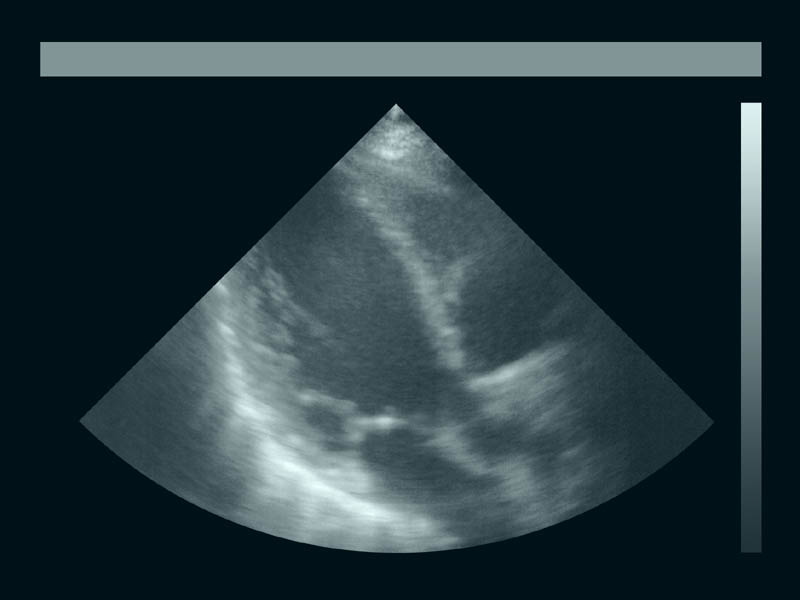

Herz-Frontalansicht

Melitta Moschik HUMAN INTERFACE 2001

Sono-/Computergrafischer Film

je 60 x 80 x 12 cm